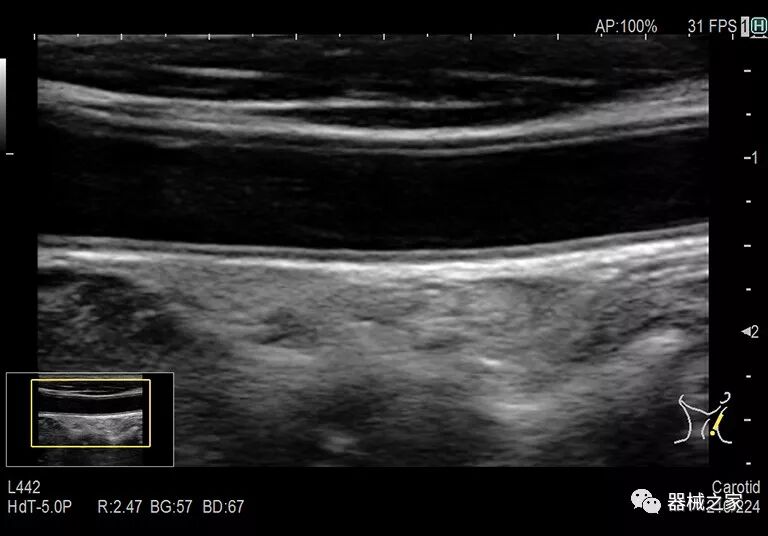

在几年前,超声波无法对小型慢流血管中的血流进行成像,但现在有少数供应商提供具有此功能的系统。该特征提供了另外一种检查病变以指示癌症或炎症的方法。其中一个是佳能Aplio 900 CV系统,它可以显示毛细血管中的血流量。日立的Arietta 65中程系统提供了一种可视化小血管的功能,可以更好地观察肾脏等器官的灌注情况。三星RS85还提供MV-Flow可视化慢流微血管结构。

Baptist Health South Florida成为去年秋天西门子医疗保健公司Acuson Sequoia的首个商业安装网站。该系统将有助于增强胃肠病学,初级保健和减肥专业的成像能力。Sequoia可实现高分辨率成像,自动适应患者的体型和个人身体特征,有助于更加自信的诊断。它适应患者的组织密度,刚度和超声波束吸收的生物声学变化。这使得系统可以穿透高达40厘米而不会因衰减回波信号而导致图像质量下降。